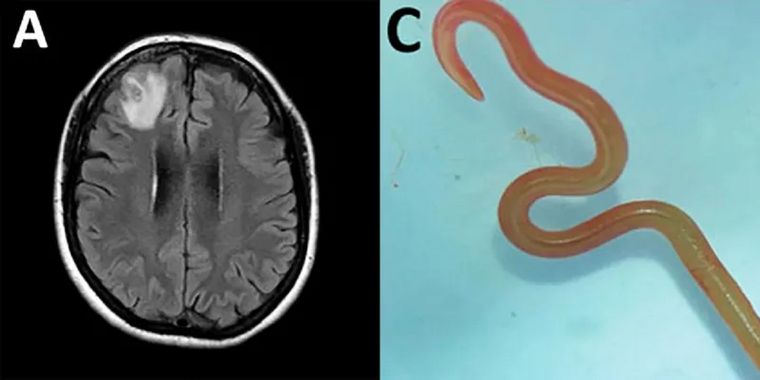

5. Un gusano vivo en el cerebro

Por primera vez en el mundo, unos científicos extrajeron un gusano vivo de 8 cm del cerebro de una mujer australiana.

La "estructura en forma de cuerda" fue extraída del lóbulo frontal dañado de la paciente durante una intervención quirúrgica en Canberra el año pasado, pero el informe de la operación no se publicó hasta este año.

Ingresó al hospital a finales de enero de 2021, y un escáner reveló "una lesión atípica en el lóbulo frontal derecho del cerebro".

Según los médicos, el parásito rojo pudo permanecer vivo en su cerebro hasta dos meses.

Se cree que este es el primer caso de invasión y desarrollo de una larva en el cerebro humano, según afirmaron los investigadores en la revista Emerging Infectious Diseases, que informó del caso.